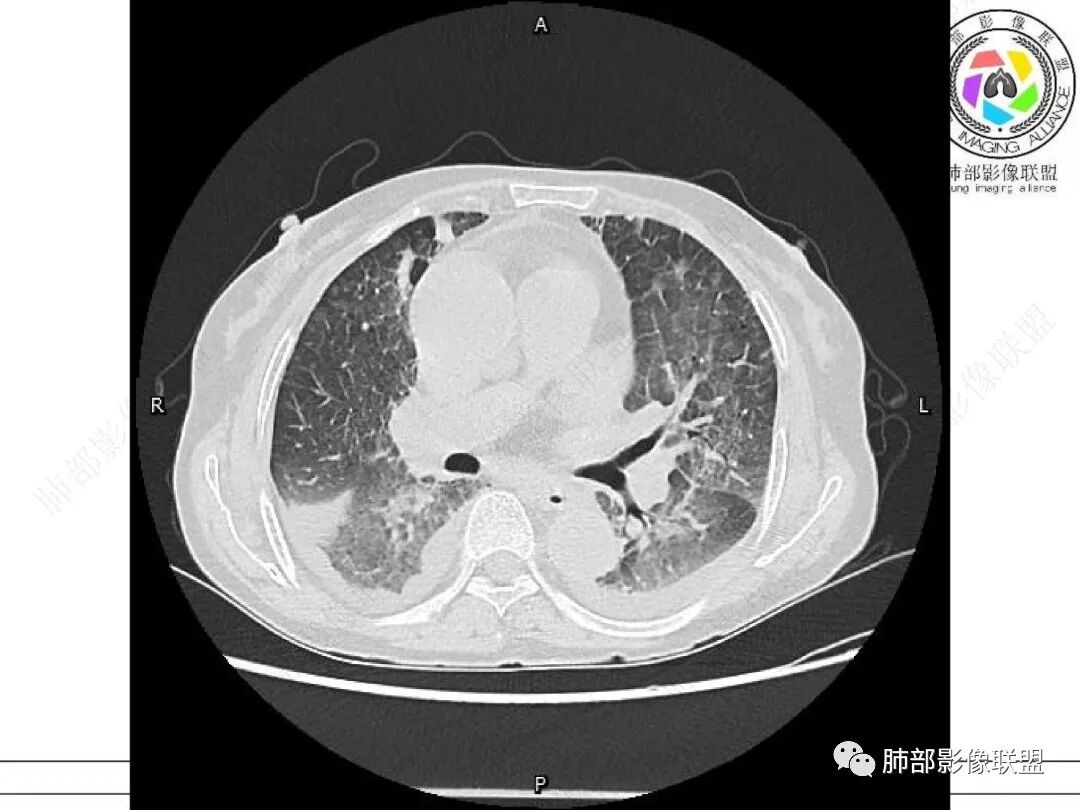

心脏大,胸腔积液,小叶间隔增厚,双肺磨玻璃影,考虑存在肺水肿,另双肺间质性炎性,类风关病史,考虑CTD-ILD,左肺上叶结核可能。

两肺叶后肋膈角区见多发蜂窝状结构破坏表现,双肺叶小叶间隔增厚,左肺上叶后段及舌段和右肺中叶胸膜炎性肉芽肿特点,双侧胸腔少量积液,有类风湿性关节炎治疗史,结缔组织相关性间质性肺病。

老年女性,有高血压糖尿病及类风湿性关节炎病史,发病前发烧。影像学两肺弥漫性磨玻璃影及斑片影,有渗出性病变亦有间质性改变,支气管血管束增粗,有牵拉扭曲有小气管扩张及间质增厚,两肺下叶胸膜下少许蜂蜜状影。两侧胸腔积液。考虑类风湿性关节炎肺内浸润?合并真菌感染?

老年女性,类风湿关节炎病史多年。发热。以两肺下叶为主弥漫磨玻璃及网格状透亮影,透亮度减低,局部小蜂窝状改变;两肺胸膜下散在几枚实性病灶;双侧胸腔积液。考虑RA-ILDNSIP

女,71,外阴疼痛2周,发热1周。类风关、高血压、高血糖、卵巢囊肿、肠粘连、胆囊结石等病史及相关药物治疗史。胸部CT:两肺弥漫磨玻璃,血管束增粗,两下肺后肋膈角多发蜂窝,对称分布,双侧胸腔少量积液,纵隔窗心脏大血管影明显增宽。考虑混合性病变,CTD-ILD,并肺水肿?并PJP?。

①影像表现复杂:较弥漫间质性改变,对称磨玻璃密度为主,小叶间隔增厚,有一定重力分布趋势,未见明显纤维化,气囊及蜂窝位于肺边缘,未见典型“月弓征”。心脏影增大,双侧胸腔积液。

这即可见于间质性肺病,也可见于真菌感染(如PJP)、病毒感染,类风湿,以及肺水肿等等。

一般而言,如存在磨玻璃密度影浑浊,有重力分布趋势,肺表面蜂窝影,胸腔积液等等,并不常见于单纯PJP,除非其他因素叠加。

患者存在肺水肿应当是合理的解释。其他旁证还有,心脏影增大,肾小球滤过率降低,双侧胸腔积液等等……